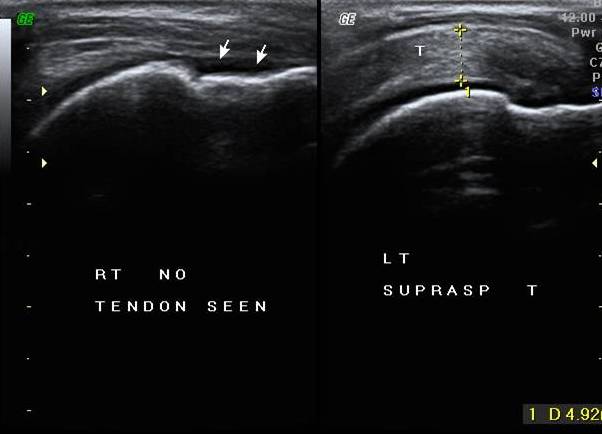

CASE 3 - FULL THICKNESS SUPRASPINATUS TENDON TEAR WITH COMPLETE RETRACTION , BARE TUBEROSITY SIGN

A 75 years old man with h/o fall , & was unable to abduct shoulder

AT US - There is complete absence or nonvisualsation of supraspinatus tendon at its position , s/o Naked/ Bare tuberosity sign . In this case deltoid muscle is directly resting on humeral head . [see Figure 3]

Figure 3 – Nonvisualisation of supraspinatus tendon ,& deltoid muscle is directly resting on humeral head – Bare /Naked tuberosity sign